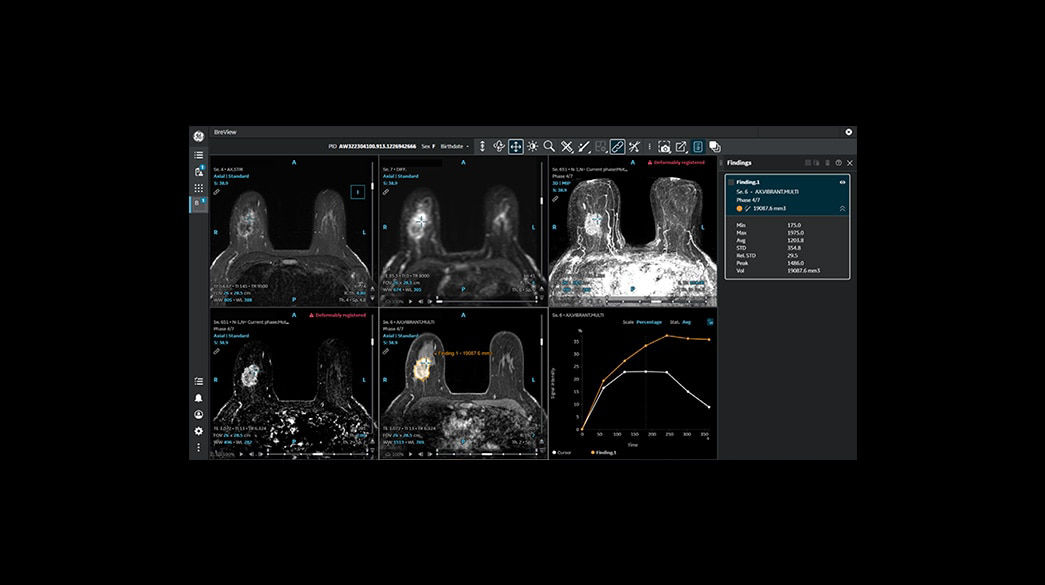

Quantifiable

Provides quantitative and actionable information